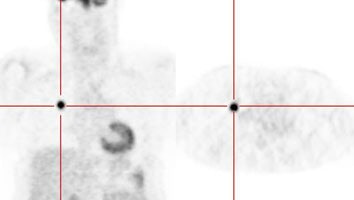

Small nodule: The patient shown below presented for evaluation of an 8 mm right lower lobe pulmonary nodule (white arrow). The PET scan was negative, but because of the lesions small size, the lack of uptake is not definitive for a benign lesion. Follow-up CT imaging will be required to document that the lesion remains stable over time. |